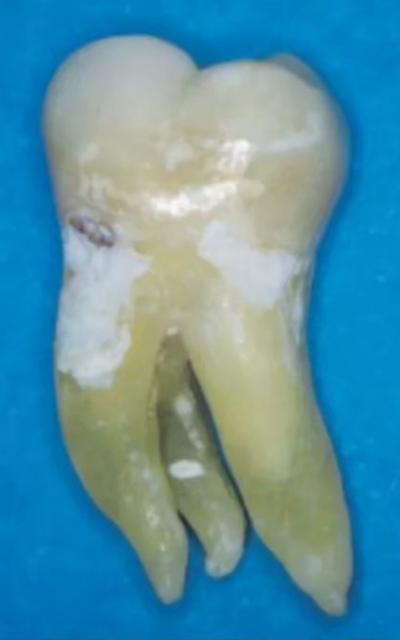

異于雙根的下頜第一磨牙的解剖形態(tài)變異主要為存在一個額外的位于遠(yuǎn)舌側(cè)【radix entomolaris(RE)】或近頰側(cè)【radix paramolaris(RP)】的牙根(圖 13)。在白種人和非洲人中發(fā)生這種牙根異常形態(tài)的概率不超過 5%,然而在黃種人中(比如中國人、因紐特人、印第安人)遠(yuǎn)舌根發(fā)生率在 5%至超過 30%之間。位于頰側(cè)的近頰根罕見,發(fā)生率低于 0.5%(。遠(yuǎn)舌根的外形大小可從小圓錐形變化至正常長度和根管的“成熟的”牙根。

一般來說,遠(yuǎn)舌根比遠(yuǎn)頰根和近中根小,可能獨立于或部分融合于其他牙根。臨床治療過程中,當(dāng)懷疑存在額外的牙根時,需要根據(jù)準(zhǔn)確的放射學(xué)診斷、臨床檢查、開髓洞型預(yù)備進行判斷。在術(shù)前的放射片中,若遠(yuǎn)中根輪廓或根管的視野或外形不清楚,可能表明存在“隱藏的”牙根。在近中或遠(yuǎn)中成 30 度角的方向上拍攝第二張放射片,通??梢燥@示遠(yuǎn)舌根的輪廓。

使用牙周探針對牙冠或牙頸部形態(tài)進行臨床檢查有助于發(fā)現(xiàn)額外的牙根。一個額外的牙尖(副磨牙結(jié)節(jié),tuberculum paramolare)或明顯突出的遠(yuǎn)頰或遠(yuǎn)舌小葉,伴有頸部的突出,可能表明存在額外的牙根。遠(yuǎn)舌根的根管口位于主要的遠(yuǎn)中根管的近舌側(cè),因此開髓洞型需要預(yù)備成矩形或梯形。使用牙髓探針仔細(xì)檢查髓室底的暗色的發(fā)育溝,可以精確的定位遠(yuǎn)舌根根管口。